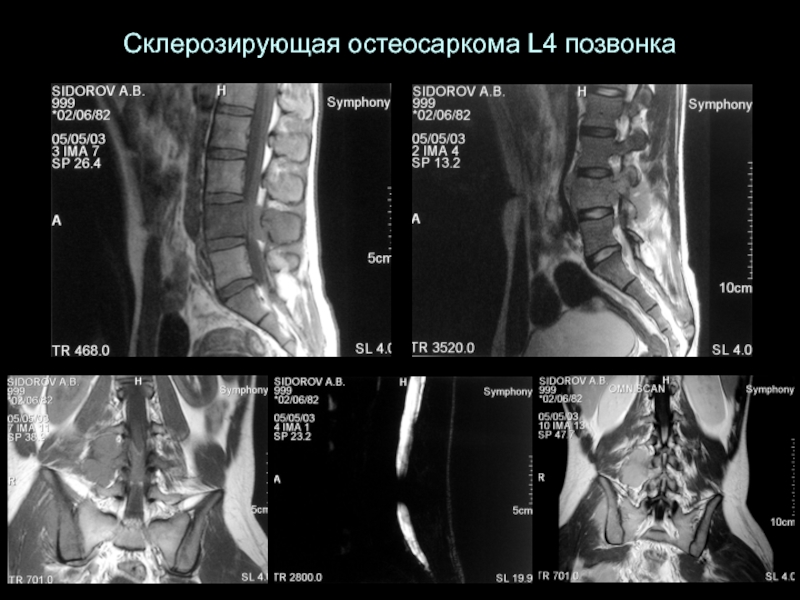

Слайд 16Склерозирующая остеосаркома L4 позвонка

Склерозирующая остеосаркома L4 позвонка